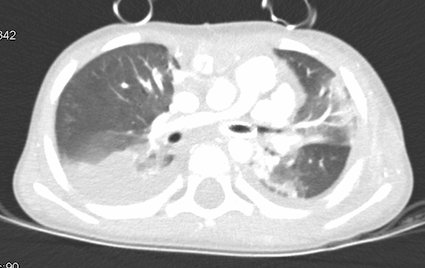

Dopo 2 mesi il piccolo è stato sottoposto a intervento di rimozione dell’anello vascolare e plastica del ramo polmonare sinistro, presso un altro ospedale. Dopo qualche giorno dall’intervento, giungeva nuovamente alla nostra attenzione per ipoalimentazione, calo ponderale e distress respiratorio, per eseguire Rx del torace con riscontro di “sfumato addensamento parenchimale in sede basale paracardiaca sinistra”. Pertanto, vista la storia pregressa, è stata effettuata una nuova broncoscopia che ha evidenziato paresi cordale sinistra e malacia del bronco principale sinistro, per cui il piccolo veniva ricoverato per iniziare terapia antibiotica ev. Tuttavia, per la persistenza della riduzione del MV a sinistra e accessi di tosse catarrale ha eseguito angio-TC polmonare, che mostrava bronco principale sinistro collassato per circa 7-8 mm e bande di addensamento parenchimale, come da atelettasia, nel segmento mediale del lobo medio e nel segmento inferiore della lingula (Figura 3).